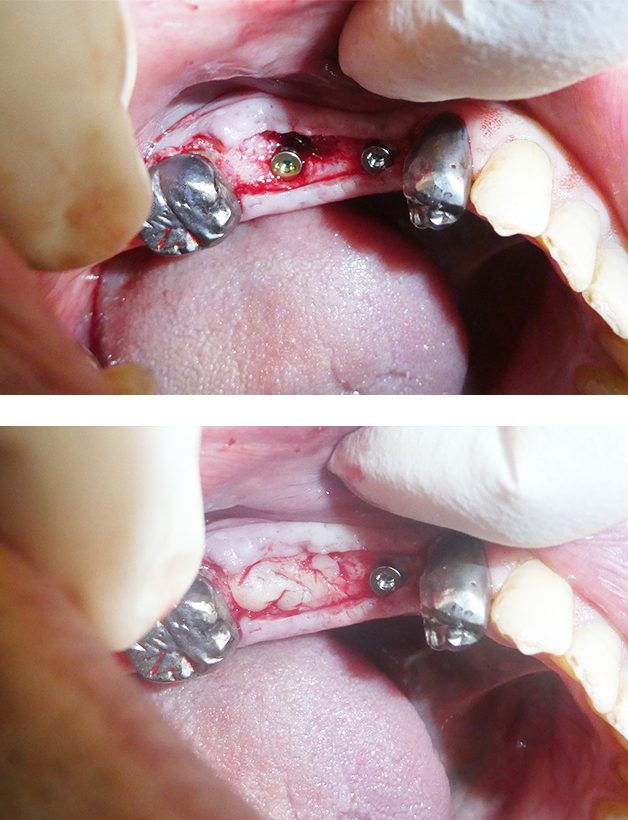

血小板を使用した再生医療

失った骨を再生するために、人工骨や人工膜、採血した血液から血小板を分離して治療に使用します。

インプラントを埋入するのに必要な足場作りをしっかりと行なっていきます。

インプラント埋入

通常の埋入手術であればおよそ20分から30分程度で終了します。

可能な限り手術中の無駄は省き、短時間で手術を終えれるよう配慮しています。

2次手術

インプラントと被せ物をつなぐアバットメントを口腔内に出していくための手術です。